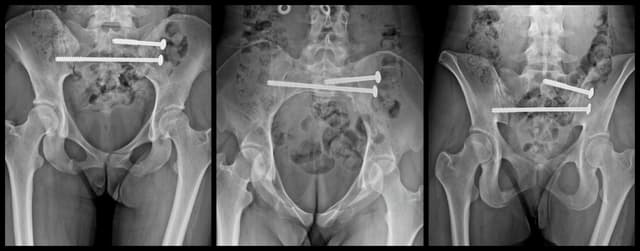

Posterior Sacroiliac Joint Fixation

Pre-op

Post-op